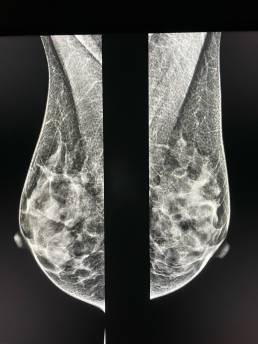

54-year-old female, routine mammogram.

MammoScreen® points to an increase in opacity of the outer quadrants of the right breast.

On the tomosynthesis performed from the front, the image does not jump to the eyes.